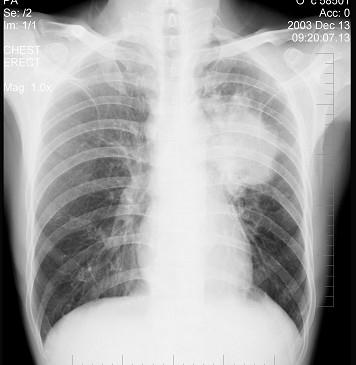

问题 女性,51岁,胸痛数月,痰血2天,X线检查见图,最可能的诊断是 ( )

选项 A.左肺癌 B.左侧炎性假瘤 C.左侧纵隔肿瘤 D.左肺转移瘤 E.支气管扩张

答案 A